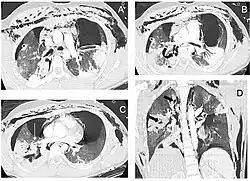

A radiografia de tórax é a técnica inicial de imagem usada para diagnosticar a lesão traqueobrônquica.[17] A imagem pode não mostrar sinais em pacientes assintomáticos.[15] Indicações de lesão traqueobrônquica em radiografias incluem deformidade na traqueia ou defeito na parede traqueal.[17] Radiografias também podem mostrar enfisema cervical, ar nos tecidos do pescoço.[2] Raios X podem revelar lesões associadas e sinais como fraturas e enfisema subcutâneo.[2] Se o enfisema subcutâneo ocorre e o osso hioide aparece em uma radiografia posicionado anormalmente alto na garganta, pode indicar que a traqueia foi seccionada.[4] A lesão traqueobrônquica também é suspeita se um tubo traqueal aparece deslocado em uma radiografia, ou se seu balonete parece mais cheio que o normal ou protrai através de um rasgo na via aérea.[17] Se um brônquio é completamente rasgado, o pulmão pode colapsar para fora, em direção à parede torácica (em vez de para dentro, como no pneumotórax usual), pois perde a fixação ao brônquio que o mantém centralizado.[6] Em uma pessoa deitada de costas, o pulmão colapsa em direção ao diafragma e às costas.[23] Esse sinal, descrito em 1969, chamado sinal do pulmão caído, é patognomônico [en] da lesão traqueobrônquica (diagnóstico exclusivo, pois não ocorre em outras condições); no entanto, é raro.[6] Em até um em cinco casos de trauma contuso com lesão traqueobrônquica, não há sinais na radiografia torácica.[23] A tomografia computadorizada detecta mais de 90% das lesões traqueobrônquicas por trauma contuso,[3] mas nem raios X nem tomografia substituem a broncoscopia.[6]